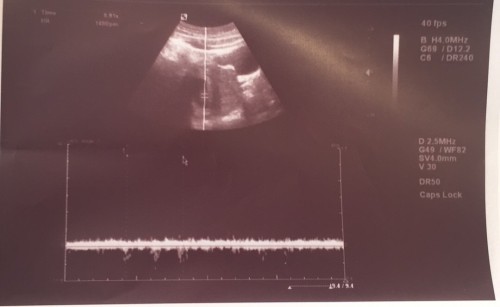

Hello everyone, 1st time preggy here nag pa check kasi ako kanina sa OB tapos sabi ng OB placenta pa lng yung nakita tapos sabi nya di sya sure kung ilang weeks na akong buntis. Sure na po ba yun na buntis talaga ako? Tuloy tuloy na po ba ito? P.S di po ako normal ang dalaw ko minsa lng po talaga ang dalaw ko

baka 3-5 weeks ka palang sis kaya sac pa ang nakikita. wala pang laman. yung sakin. 6 weeks nga sac pa lang din. pag 8 weeks na onwards dun na nakita ang embryo and heartbeat ni baby.